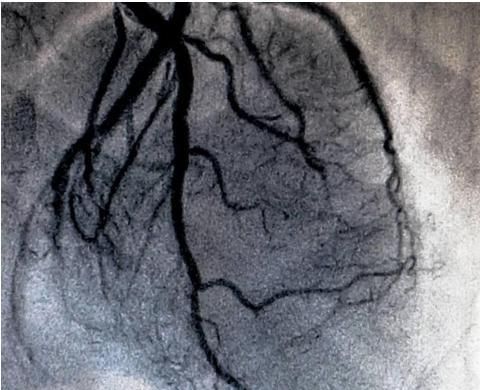

急诊冠脉造影提示前降支近端血栓形成,植入支架后血流恢复正常

scad的冠脉造影影像

冠脉造影图片

正常心脏冠脉造影图片